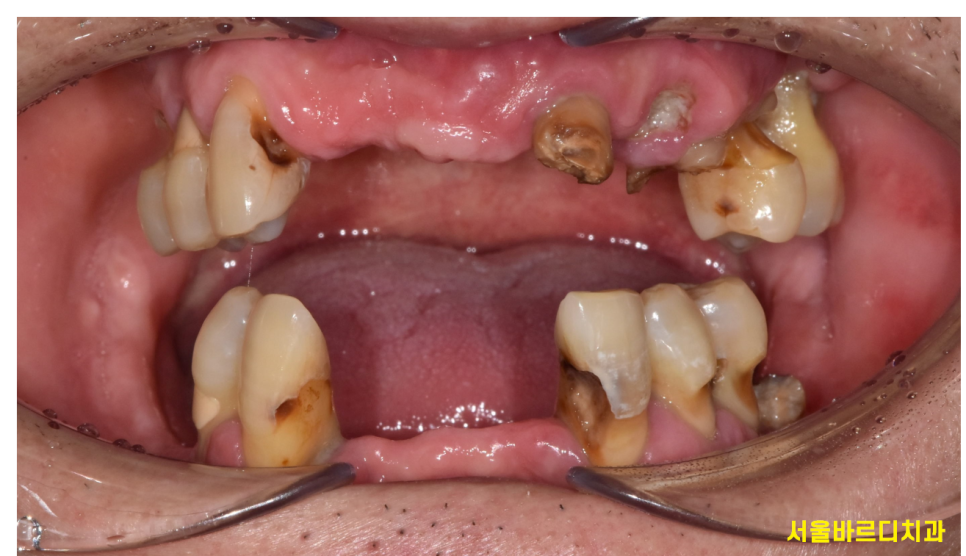

내원 이유: 앞니 먼저 만들어주세요

240423

치아 전반적으로 충치가 심하고

앞니의 경우는 뿌리만 남은채로 내원하신 환자분입니다.

사회생활도 해야하고

사람들이 자꾸 치아만 보는 것 같다고

앞니 먼저 치료를 원하신다하셨어요.

식사가 불편하지 않으셔요~?

어금니를 치료해야 식사를 하실텐데요..

여쭤보니..

어차피 지금도 식사는 불편하기 때문에

사람들의 시선이 더 중요하다 말씀해주시더라고요.

240423 앞니 어금니 둘다 문제가 생겼어요